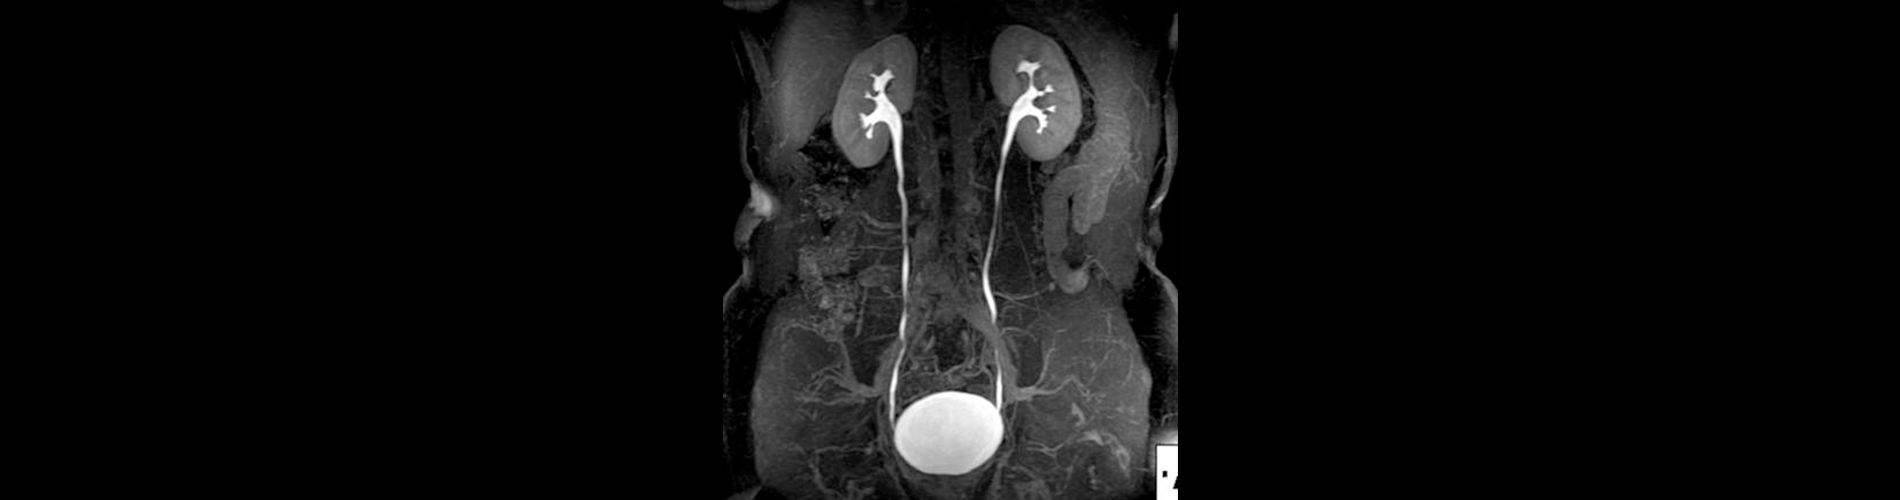

Ürografi MR Nedir?

• Hedef Bölge: Böbrekler, üreterler (idrar yolları), mesane ve çevresindeki yapılar.

• Yüksek Çözünürlük: İdrar yollarının detaylı anatomik ve fonksiyonel görüntülerini sağlar.